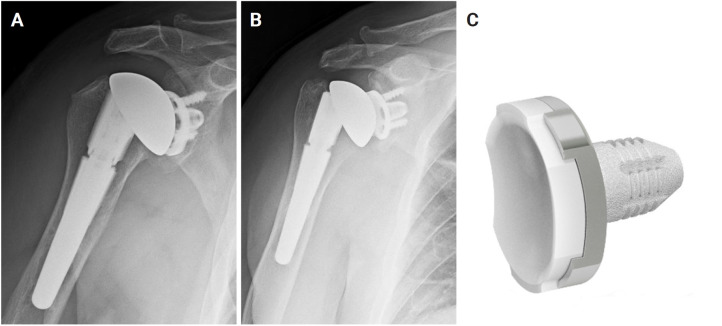

Abstract Image